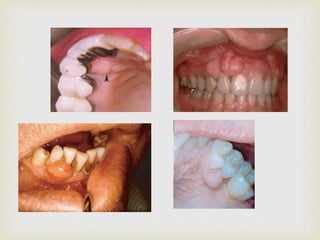

 Nodular mass

 Pedunculated or sessile

 Usually arises from the interdental papilla

 Red to pink in colour; usually ulcerated

 Mostly less than 2cms

 DIFFERENTIAL DIAGNOSIS

 Red lesions: pyogenic granuloma

 Pink non-ulcerated lesions: irritational fibroma

 RADIOGRAPHICALLY: superficial erosion